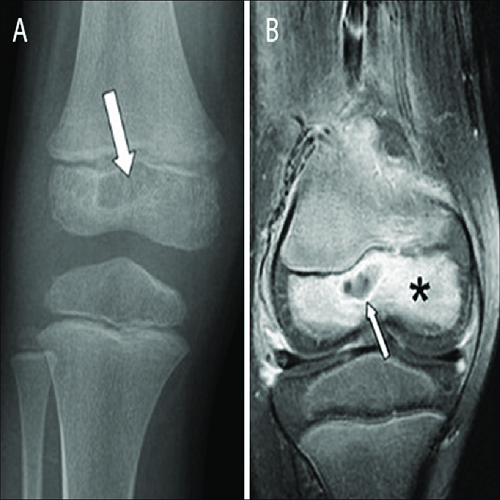

Artroskopik Menisküs Onarımı Nedir? Artroskopik menisküs onarımı, diz eklemindeki menisküs adı verilen kıkırdak dokusunun, minimal invaziv bir cerrahi prosedür olan artroskopi yöntemiyle onarılması işlemidir. Menisküs, diz eklemleri içinde bulunan C şekilli kıkırdak yapıdır ve ek yüzeylerin düzenli bir şekilde yük görünümünü sağlar. Ancak travma, aşırı zorlanma veya yaşlanmaya bağlı olarak menisküs yırtılabilir. Artroskopik menisküs onarımı,…